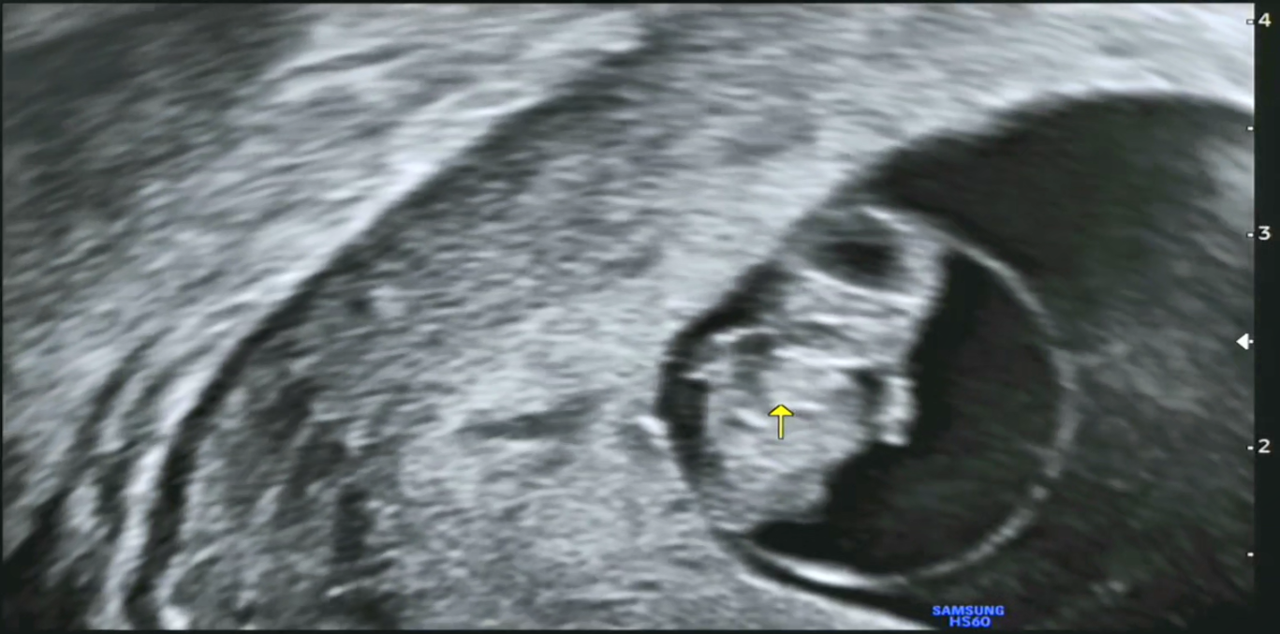

오전 10시쯤 되니 딸아이로부터 카톡을 통해, 우리 '팡팡이의 8주 0일 초음파' 동영상이 날아왔습니다.

임신 7~8주쯤 되면 기관의 형성기라고 해서 아기의 뇌와 몸의 기초가 만들어진다고 하고, 심장이 형성되면서 혈액이 몸으로 보내지기 때문에 심장을 확인할 수 있다고도 하네요.

그리고 이때쯤 되면 머리와 몸의 크기가 같은 2등신이 되고 손발이 구별된다고 해서, 영상을 한번 캡처해 보았습니다. 제가 딸보고 머리가 크다고 했더니 '하리○ 젤리곰' 같다고 하네요. 언듯 보면 '겨울왕국의 올라프' 같이 보이기도 합니다. 태명이 '울라프'도 괜찮아 보이네요.

7주0일 머리.png

7주0일 팔.png

[왼쪽-머리, 오른쪽-팔]